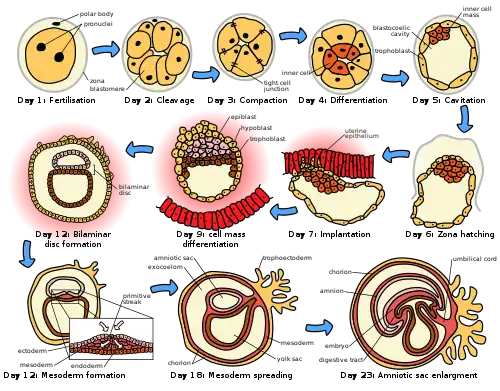

The placenta begins to develop upon implantation of the blastocyst into the maternal endometrium, very early on in pregnancy at about week 4.[17]

The outer layer of the late blastocyst, is formed of trophoblasts, cells that form the outer layer of the placenta. This outer layer is divided into two further layers: the underlying cytotrophoblast layer and the overlying syncytiotrophoblast layer. The syncytiotrophoblast is a multinucleated continuous cell layer that covers the surface of the placenta. It forms as a result of differentiation and fusion of the underlying cytotrophoblasts, a process that continues throughout placental development. The syncytiotrophoblast contributes to the barrier function of the placenta.[18]

The placenta grows throughout pregnancy. Development of the maternal blood supply to the placenta is complete by the end of the first trimester of pregnancy week 14 (DM).[17]

The trophoblast is the outer layer of cells of the blastocyst (see day 9 in Figure, below, showing the initial stages of human embryogenesis). Placental trophoblast cells have a unique genome-wide DNA methylation pattern determined by de novo methyltransferases during embryogenesis[47]. This methylation pattern is principally required to regulate placental development and function, which in turn is critical for embryo survival[47].